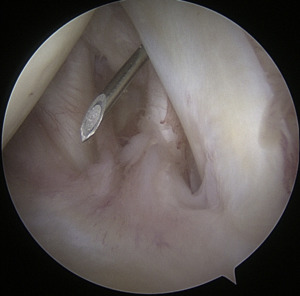

Instrumentation

When it comes to shoulder arthroscopy, the most common arthroscope utilized is the 4.0 mm 30 scope. A 30-magnification scope is sufficient for most situations. An arthroscopic-assisted coracoclavicular reconstruction, subscapularis repairs, Remplissage procedures, glenohumeral ligament lesions, and humeral avulsion can all benefit from the use of a 4.0-mm 70 arthroscope, which should always be on hand. There should be a large selection of cannulas accessible, and they will differ according on the operation being carried out.25

As the principal penetrating instruments, 5.5-mm blunt-tipped cannulas are often used for portal insertion. Blunt tips are preferred to reduce the likelihood of iatrogenic harm, especially to articular cartilage. Because they are easily passable by the majority of arthroscopy passing devices, 8.25-mm cannulas are often employed for “instrumentation” portals. In addition, cannulas of 6.5 mm or less are commonly used in suture management. Cannulas that are threaded or have locking mechanisms are preferable since they are less likely to come free from the joint. In most cases, one of two methods can be employed: gravity or a pump system. Sufficient management of pressures, usually approximately 60 mm Hg, is necessary to avoid significant soft-tissue edema, which can complicate the use of cannulas and instruments.25

Standard Portal Placement

A traditional posterior portal would be placed at the “soft spot” of the infraspinatus’s raphe. The standard placement is 2 centimeters inferior and 2 centimeters medial to the posterolateral border of the acromion, however this can change according to the patient’s size. It is possible to make a portal incision after inserting an 18-gauge spinal needle into this region to roughly follow the correct course. The posterior capsule is shattered by inserting a blunt trocar into the joint and directing it toward the coracoid.6

Preliminary surgical planning will establish the exact location of the anterior portal. Arthroscopy techniques for rotator cuff or biceps tenodesis usually include positioning the anterior portal centrally in the rotator interval, near the subscapularis tendon. It is common practice to use two anterior portals while performing arthroscopy on labral disease. The anteroinferior portal, which is often the working portal, is typically located around the subscapularis tendon. An extra portal called the anterosuperior portal may be used for suture inspection or shuttletling without damaging the supraspinatus tendon. Its location is directly above the biceps tendon or just slightly ahead of it. A common technique for creating these portals is the “outside-in” approach, which involves inserting a spinal needle under direct arthroscopy view to determine the correct portal location.6